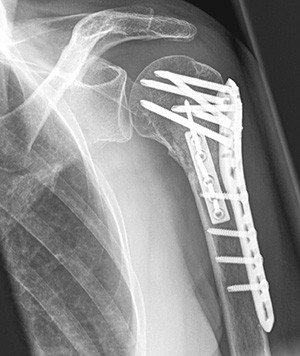

Ist es beim Unfall zu einer erheblichen Verschiebung der Knochenfragmente gekommen, sind die Chancen auf ein gutes Ausheilen und Wiedergewinnen der Schulterfunktion ohne Operation schlecht. Durch den chirurgischen Eingriff werden die einzelnen Knochenteile mittels Schrauben und Platten wieder in die korrekte Stellung und Achse zum restlichen Oberarm gebracht und fixiert. Wenige Tage nach dem Eingriff beginnt die Krankengymnastik damit das Risiko einer Einsteifung minimiert werden kann. Mit zunehmendem Alter verändert sich die Knochenqualität. Der Knochen wird fragiler und die Behandlung von Frakturen schwieriger. In gewissen Fällen kann die sichere Verankerung von Schrauben und Platten nicht mehr erreicht werden. Solchen Patienten ermöglicht das Einsetzen eines Kunstgelenks eine gute Option auf eine erfolgreiche Behandlung.